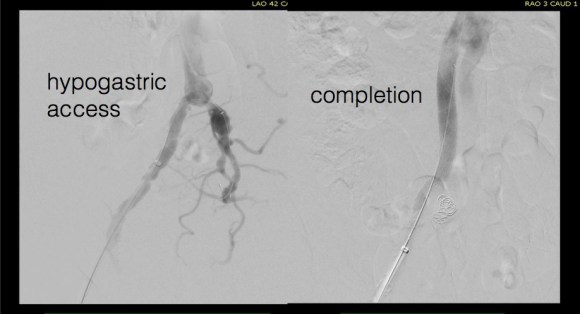

For example, take this patient who after EVAR of aortic aneurysm with AFX developed metachronous dilatation of the common iliac artery to 3.9cm with abdominal pain. The average diameter is 18.5mm. From the table, that rounds to 19mm corresponding to 283.53 square mm. If the internal iliac artery requires a 13mm graft, that is 132.73 square mm, the difference being 150.80 square mm. That corresponds to a 14mm diameter graft, but a slightly larger graft is preferred for oversizing. The external iliac artery is 8mm, and putting a 13mm Viabahn (largest available) in that would result in the B-infolding in the 8mm external iliac. Here, I bailed myself out by simply placing a 20mm AFX iliac limb extension, which by virtue of its design is resistent to infolding and tolerant of parallel grafts laid alongside in constricted channels. I found that the AFX iliac limb, a 20-13mm x 88mm length extension well suited for this.

The AFX graft limb seems to adapt to the presence of the parallel “sandwich” graft which is deployed second and ballooned last. In followup, there was shrinkage of the common iliac artery aneurysm sac and no endoleak.

Compared to my other parallel graft case treating a metachronous saccular common iliac aneurysm years after an EVAR with a Gore endograft (link), which by table calculation, resulted in 8% oversize in calculated areas, this particular technique with a large AFX graft and an appropriately sized Viabahn seemed to work well the setting of a previously placed AFX graft. It allows one to avoid hypogastric occlusion.